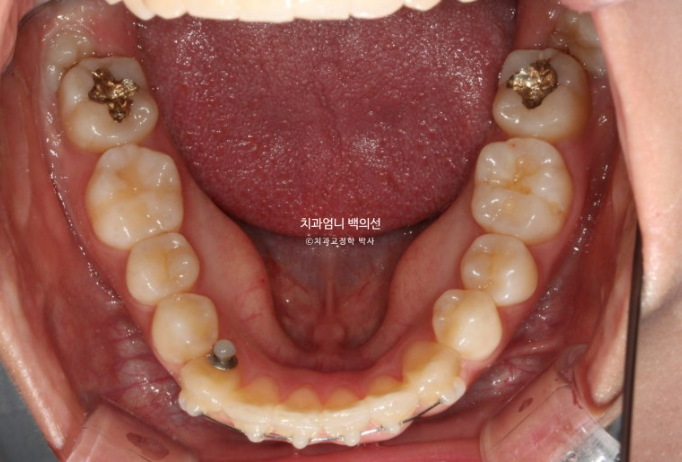

24년 9월 드디어 치료가 마무리 되었습니다.

아무래도 파란 화살표 작은어금니 덧니가 옥의티입니다.

아쉽지만 환자분이 투자한 비용과 시간, 노력 대비 앞니 부분교정만으로도 좋은 효과 봤으니 눈을 질끈 감습니다.

24.09

유지장치까지 붙은 모습입니다.

총 치료기간은 9개월입니다.